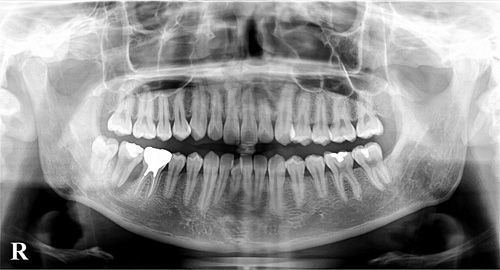

レントゲンにはお口全体を撮影するパノラマレントゲンと2~3本の歯を撮影するデジタルレントゲンがあります。

大きなサイズのパノラマレントゲンは、顎の骨の内部の病気や歯周病の進行、大まかな虫歯、親知らずの状態、歯の並びなどを確認することができます。